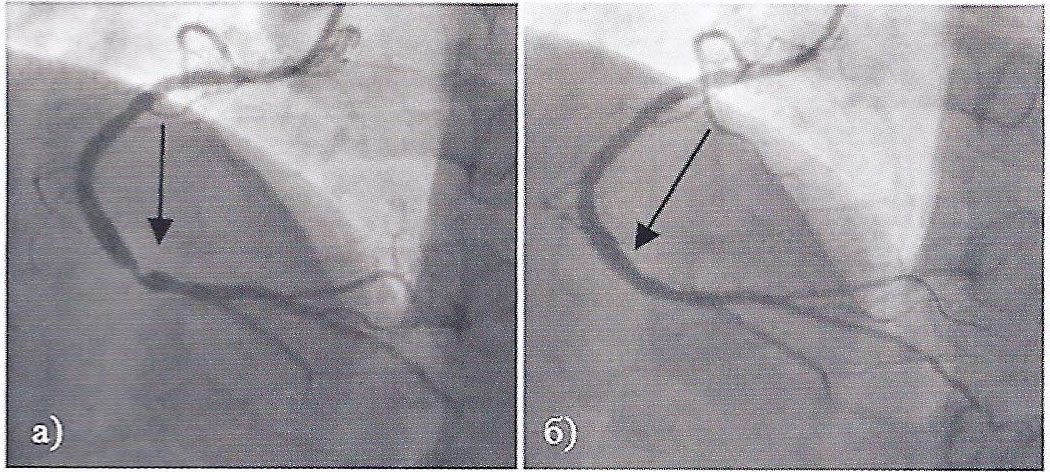

Вентрикуло-перитонеальный шунт: Показания и применение

Раздел: Фотоальбом решений